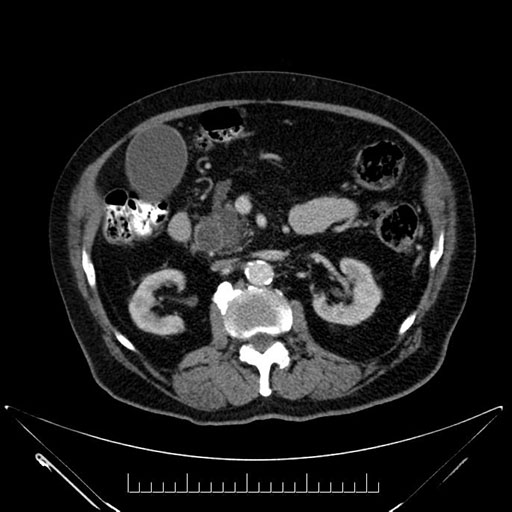

Imaging Analysis

Look through the patient's CT scan to identify any areas of concern for the necessary procedure.

Based on your CT findings, which issue(s) would give reason for "planned slowing down moment(s)" in this case?